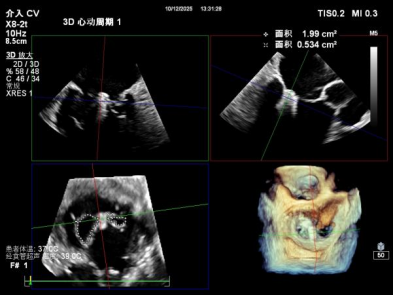

【术中操作(含关键步骤超声)】

鉴于患者术前心功能差、多支架植入的特殊情况,手术全程需兼顾“精准操作”与“保护心功能”双重要求:在全麻与经食道超声的协同引导下,团队先突破心功能受损导致的术野稳定性难题,稳步经心尖建立手术轨道与输送鞘;随后聚焦二尖瓣2偏3区精准置入一枚Ⅱf型夹合器,成功攻占这一解剖位置深、毗邻结构敏感、容错率极低而操作难度陡增的区域。

术前术后反流对比

【术后一周复查心超提示】二尖瓣钳夹术后,二尖瓣反流(轻度),夹合器固定,瓣口呈双孔结构,内外侧孔分别见微量反流,反流束VC分别 0.15cm、0.18cm,估测有效瓣口面积约2.5c㎡,舒张期瓣口前向最大血流速度 1.2m/s,平均压差3mmHg,左室射血分数(EF)值提升至35%,心功能显著改善。目前患者已顺利康复出院。